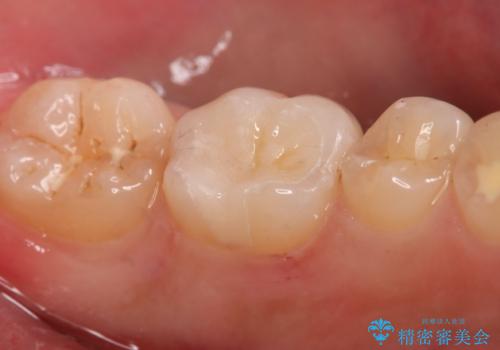

- 左下6番の治療のやり直しを希望し来院された患者様です。

保険の材料が劣化し段差や隙間ができてしまっている状態です。

自費の治療を希望されたため切削量・形態を考慮し、セラミックインレーでの治療を計画しました。